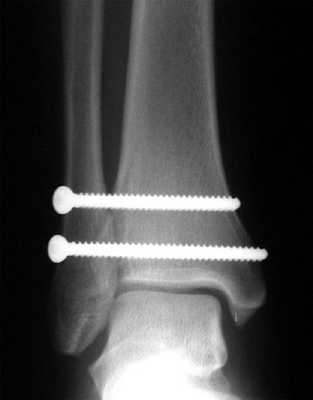

В подавляющем большинстве случаев возникает необходимость в оперативном лечении. Классическая методика заключается в фиксации синдесмоза позиционными винтами. Для этой цели подойдут 3,5 или 4,5 мм синдесмозные винты проведённые через 3 или 4 кортикальных слоя на 2-5 см выше дистального плато большеберцовой кости.

Установку винтов лучше производить в положении тыльного сгибания стопы, что позволяет предотвратить «перезатягивание». В послеоперационном периоде потребуется 6-12 недель ходьбы с костылями без нагрузки на оперированную конечность, с последующим удалением винтов.

Собственно фиксация дистального межберцового синдесмоза возможна как при помощи винтов, так и при помощи пуговчатых фиксаторов. Фиксацию лучше выполнять через небольшой кусок 1\3 трубчатой пластины, чтобы распределить нагрузку на большую площадь. В противном случае существует риск последующего перелома малоберовой кости по винту, так как он будет концентрировать на себе всю нагрузку.

В случае если фиксация производится винтом или винтами, лучше использовать трёхкортикальный метод, так как он обеспечивает менее жёсткую фиксацию, и позволяет малоберцовой кости её нормальные физиологические движения в вырезке. Четырёхкортикальные винты блокируют малоберцовую кость более жёстко. И препятствуют тыльному сгибанию стопы. После начала нагрузки четырёхкортикальные винты часто ломаютя, по той же причине.